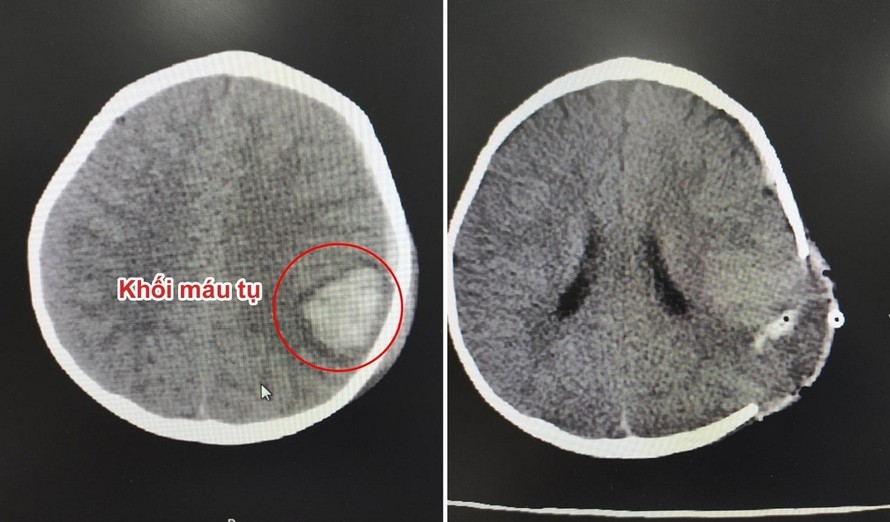

Hình ảnh trước và sau phẫu thuật lấy máu tụ nội sọ cho bé

Tiến hành chụp CT-Scanner sọ não, các bác sĩ phát hiện trên phim chụp có hình ảnh xuất huyết não dưới màng cứng và nhu mô não thái dương đỉnh trái. Ngay lập tức, bệnh nhi được thực hiện phẫu thuật lấy máu tụ nội sọ.